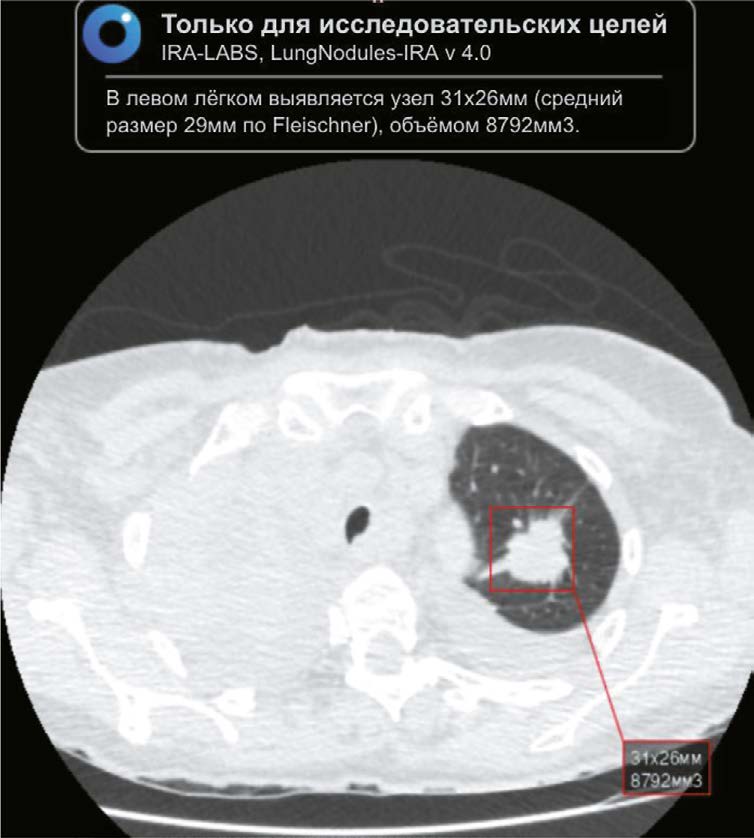

BACKGROUND: Chest computed tomography (CT) is the main modality used to diagnose lung lesions caused by COVID-19 infection. Since 2020, the use of this modality in the Krasnoyarsk krai has increased. However, the incidence of lung cancer decreased by 5.2%. The current situation has raised concerns about missing radiographic signs typical of lung cancer and has stimulated the search for new diagnostic modalities using artificial intelligence (AI) for data analysis.

AIM: The aim of the study was to evaluate the feasibility of using an AI algorithm to search for lung nodules based on chest CT data obtained during the COVID-19 pandemic to identify lung cancer.

MATERIALS AND METHODS: The retrospective study included chest CT scans of patients from Krasnoyarsk krai diagnosed with COVID-19 reported in the PACS base between 1 November 2020 and 28 February 2021. The interval between chest CT and AI analysis ranged from two years and one month to two years and five months. Chest-IRA algorithm was used. AI detected lung nodules with a volume greater than 100 mm3. The radiologists divided the results into three groups based on the potential for lung cancer. The assessment of the economic benefits of using the AI algorithm considered the cost of wages and savings in the treatment of early stage lung cancer, which affects gross regional product.

RESULTS: The AI algorithm identified nodules in 484 out of 10,500 CT scans. A total of 192 patients with a high potential for lung cancer, 103 with no signs and 60 with inconclusive signs were identified, and 112 patients with a high and moderate potential for lung cancer did not seek medical care. AI confirmed 100 (28.2%) histologically proven cases of lung cancer, with stages I–II detected in 35%.

CONCLUSIONS: The use of AI to evaluate chest CT scans demonstrates high performance in identifying lung nodules, including those in patients with COVID-19, confirming its potential use for early detection of incidental lung nodules that might otherwise be missed.